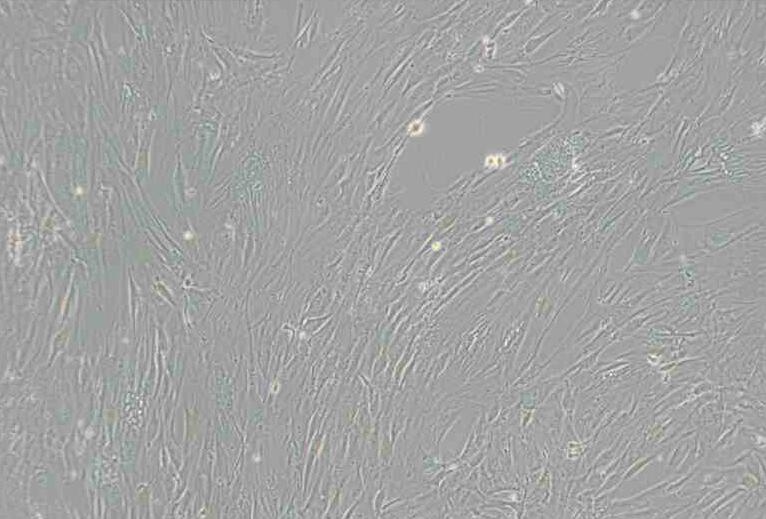

成纤维细胞样

细胞背景描述 CCD-1095Sk细胞从左乳房的活体组织切片的正常皮肤建立,病人患有乳腺浸润性导管癌并患有乳头湿疹样癌本病。这一代次的细胞已经过两次数目倍增,约可再进行10次数目倍增。

细胞形态 成纤维细胞样

生长特性 贴壁细胞